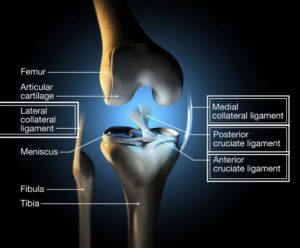

هل تعاني من تنكس او خشونة في مفصل الركبة؟ هل حالتك متقدمة او متوسطة او خفيفة؟ تعرف على كيفية اتخاذ قرار العلاج بالمشاركة مع طبيبك؟ هل العلاج الدوائي او العلاج الفيزيائي او حقن البلازما ضمن المفصل هي خيارات عن تبديل المفصل؟ احصل على استشارة معنا وسنناقش معا حالتك بدقة ونساعدك في اختيار طريقة العلاج المناسبة لوضعك.